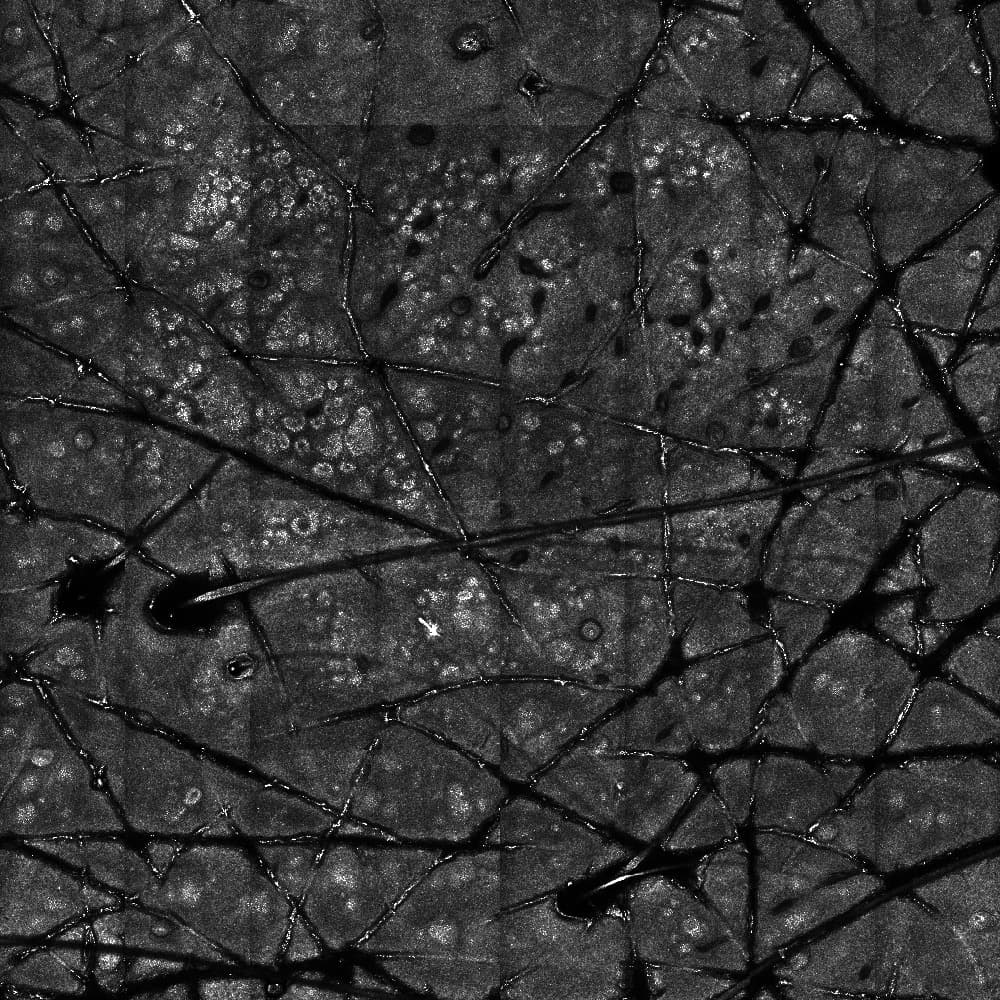

Traditional methods for diagnosing skin disorders, including cancer and fungal infections, are often slow, costly, and invasive. This solution utilises a reflectance confocal microscope combined with advanced generative AI and deep learning techniques to provide rapid, non-invasive diagnosis. This system performs virtual staining and segments infection samples without the need for traditional histological stains, reducing diagnostic time from days to minutes and lowering costs. Integrated on a cloud platform, it enables dermatopathologists to make swift, accurate decisions, significantly improving patient outcomes